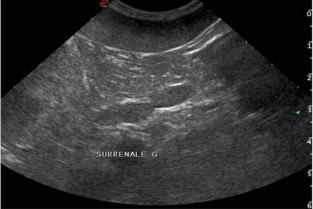

Echographie des surrénales : aspect normal et lésionnel

Cours

Aspect pathologique des glandes surrénales